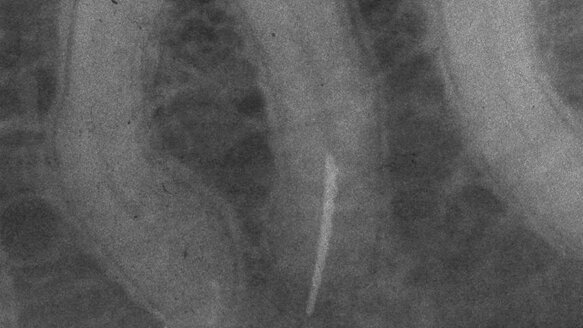

Given these problems, the K-files are used at times with a technique called balanced force, developed by Dr. James Roane. In this technique, the dentist advances the K-file with a clockwise stroke until significant resistance is encountered. He then applies apically directed pressure as the instrument is rotated counterclockwise. The apically applied pressure prevents the instrument from unscrewing itself from the embedded dentin with the counterclockwise stroke cleaving off the engaged dentin in the process. This technique has the added benefit of keeping the instrument tip centered in the canal. It is also less likely to impact debris apically because the flutes are cleansed after every counterclockwise stroke. The negatives of this technique are the time it takes to do properly and the chance of still creating a ledge in abruptly curved canals because the excessive engagement along length obscures what is happening at the tip of the instrument (Fig. 1).

The limitations of rotary NiTi are easy to observe. They are now recommended for single usage, underlining their vulnerability to breakage (Fig. 3). Glide path creation often takes the apical preparation up to a 20 or 25, with the subsequent use of NiTi creating a greater taper along length with minimal work being done apically. These goals have been imposed after the use of K-files. Imagine the increased ease of creating the glide path with the use of K-reamers, both unrelieved and relieved, and the ability to extend these preparations into complete shaping using instruments that encounter so much less resistance. They are virtually invulnerable to breakage and are consequently used several times before replacement, dramatically reducing costs in the process.